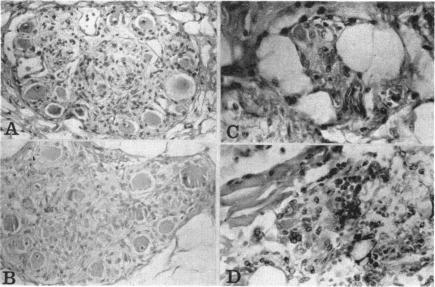

Cardiac innervation: anatomic and pharmacologic relations.